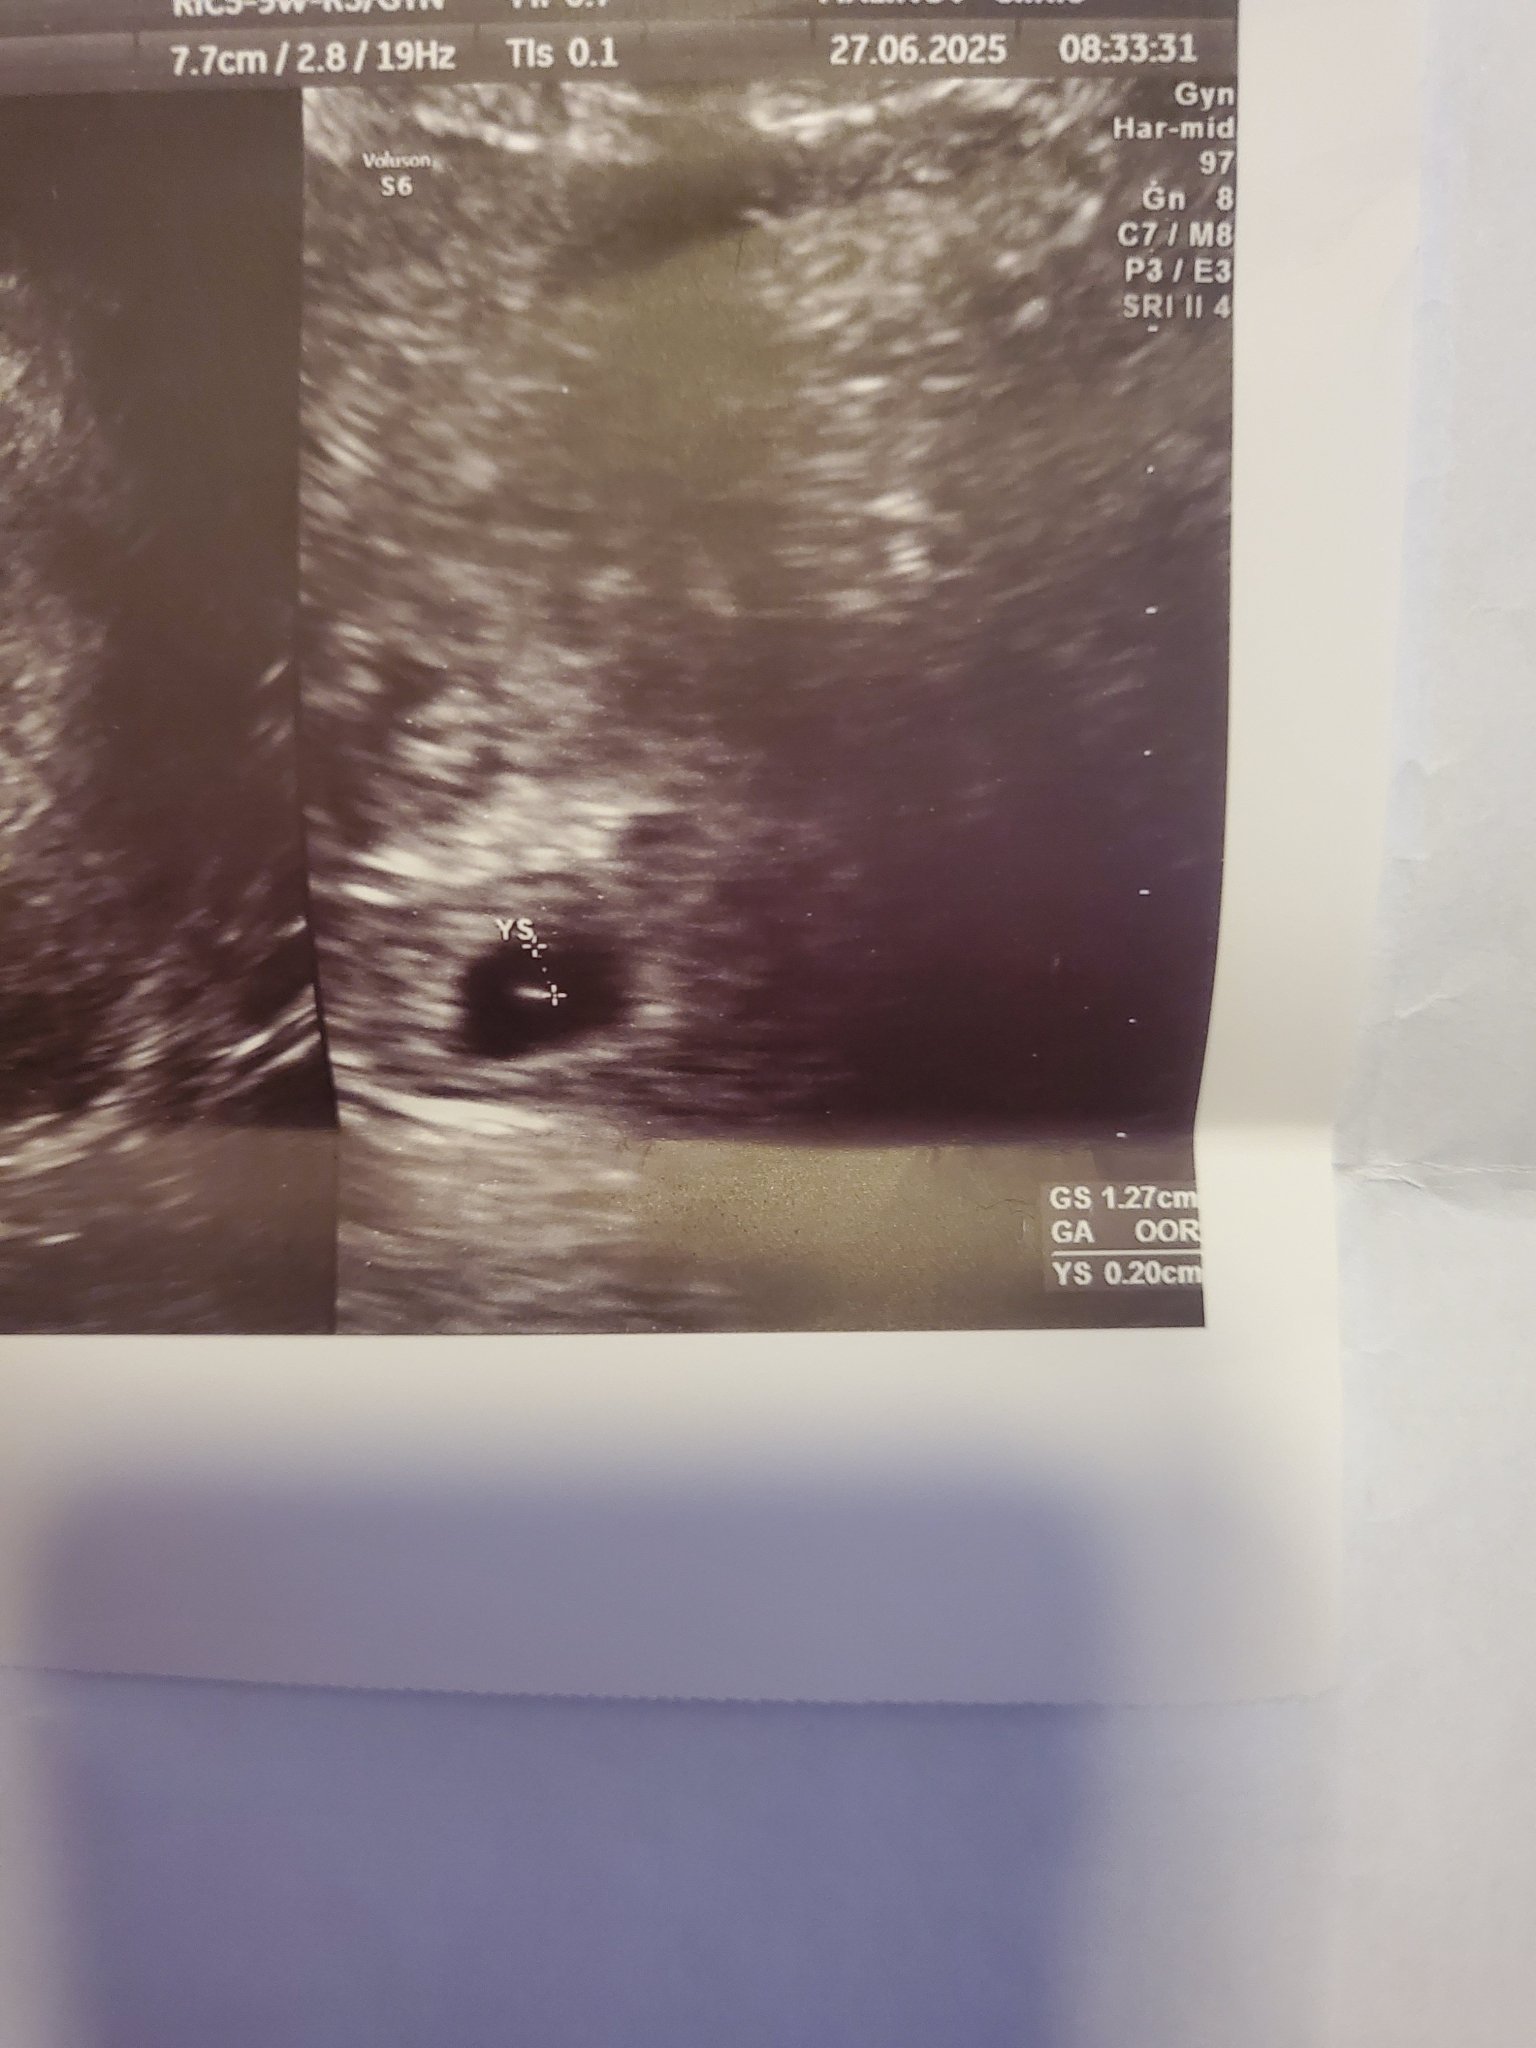

Какво представлява изображението от ехографията на 5-седмична и 2-дневна бременност?

Кога обикновено може да се види ембрионът на ултразвукова снимка?

прикачвам тази снимка тук доктора каза че е кухо яйце според вас кухо яйце ли е ?